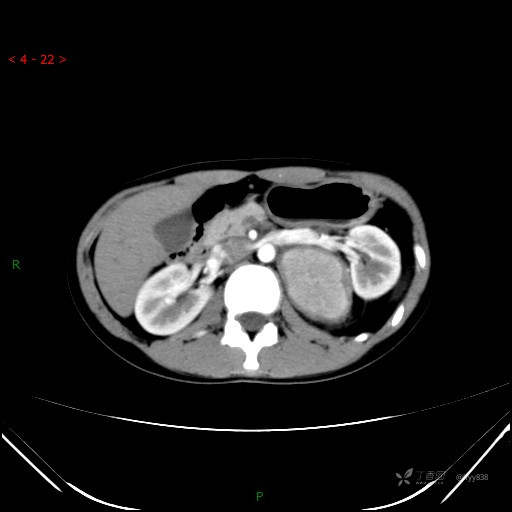

腹部CT平扫